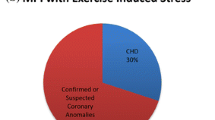

We conducted a retrospective evaluation of our experience using regadenoson for stress perfusion cardiac MR in 31 consecutive patients (25 male, 6 female) from April 2014 to December 2015. We excluded any patient requiring sedation or weighing less than 40 kg. The mean age of the patient at the time of the study was 15.8 ± 1.7 years (range 12–22 years). Twenty-nine of the patients were 18 years or younger. The mean weight of the patients was 60 ± 15 kg (range 40–93 kg) and the average body surface area was 1.67 ± 0.25 m2 (range of 1.3–2.14 m2). The clinical diagnoses are listed in Table 1. The cohort included 11 patients with D-transposition of great arteries after an arterial switch procedure (D-TGA), 9 with Kawasaki disease and coronary aneurysm, 6 with aortic root replacement, 3 who had repair of AAOCA, 1 with left ventricular hypertrophy and 1 with coarctation. All but two of the patients had a lesion considered to have an elevated risk of myocardial ischemia. The other two had a history of coarctation repair and left ventricular hypertrophy, respectively, and demonstrated nonspecific ST segment changes during an exercise stress test.